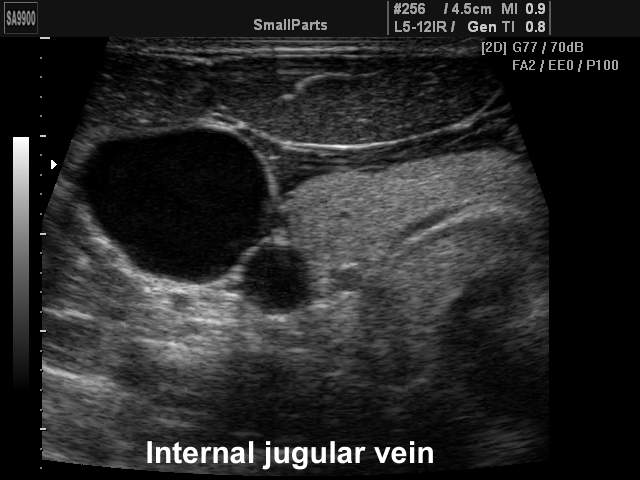

Internal jugular vein, B-mode

Internal jugular vein, B-mode (echogramm №217)

Echogramm was received by ultrasound scanner SonoAce-9900 (out of production).